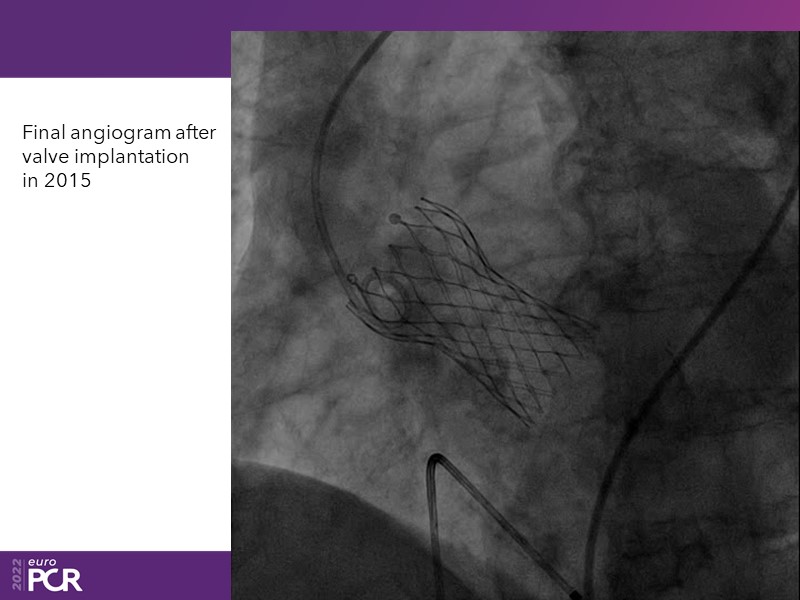

Consult this session to learn how to contribute to streamlined pre- and post-TAVI patient pathways, to discover updates on the optimised TAVI procedure and appreciate the variances in different valve designs and the long-term patient outcomes, as well as to discuss the right time of PCI in TAVI patients (steps on the procedure).